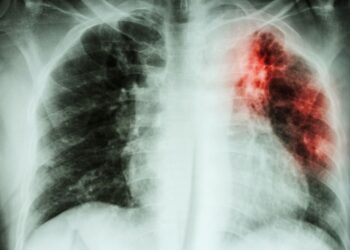

Tag: fibrosi polmonare idiopatica